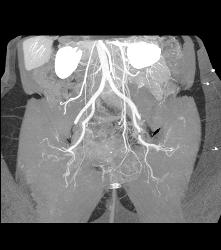

VRT and Renal Artery Mapping